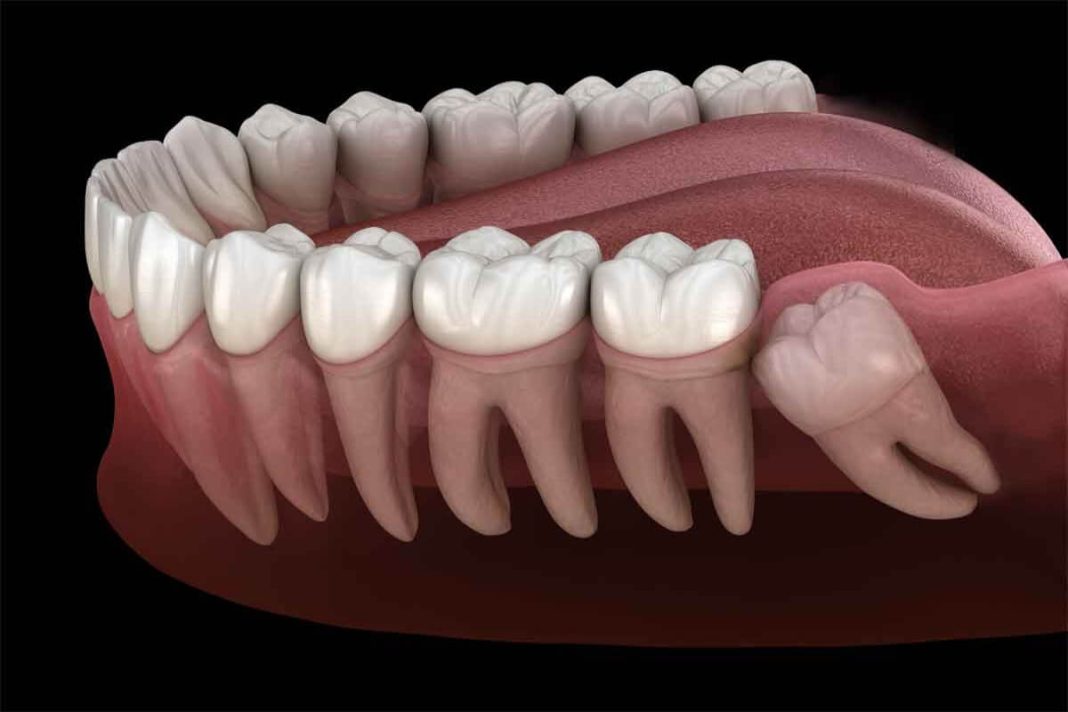

- Apiñamiento: Cuando las muelas del juicio no tienen suficiente espacio para salir correctamente, pueden empujar a los demás dientes, provocando apiñamiento y problemas de mordida.

- Infecciones: La posición de las muelas del juicio, a menudo impactadas o parcialmente erupcionadas, dificulta la higiene bucal, lo que aumenta el riesgo de caries e infecciones